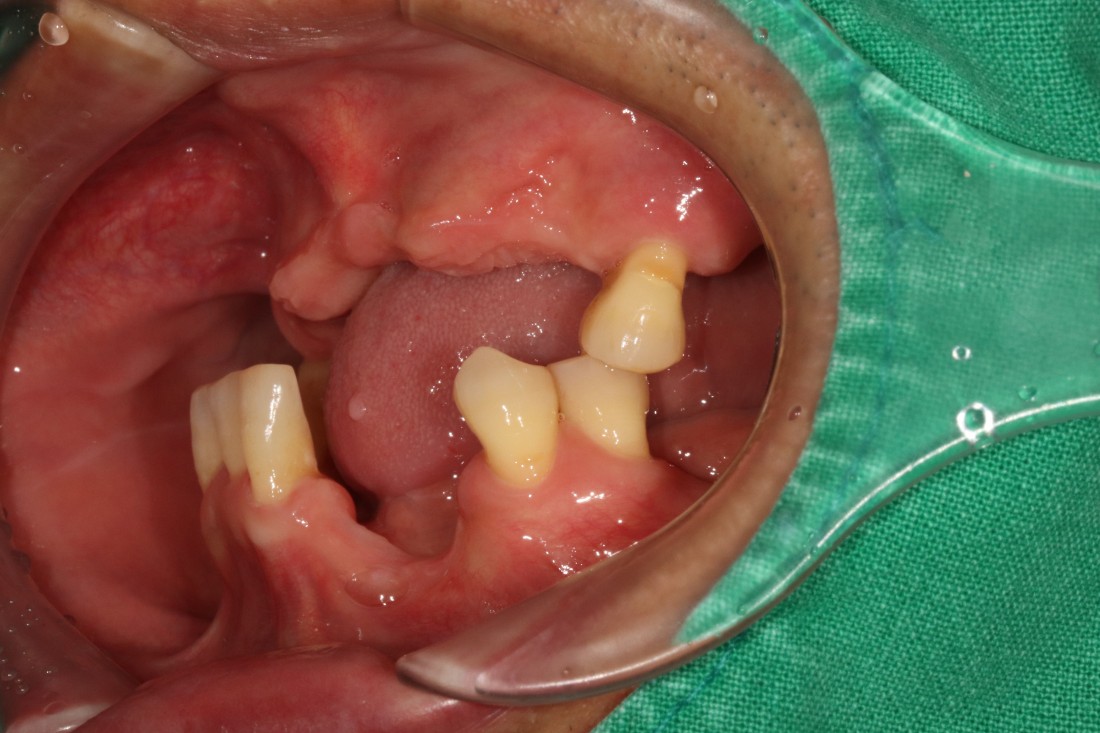

잇몸절개를 최소화 할수록

회복에 걸리는 시간도 매우 적기 때문에

고혈압/ 당뇨 등 기저질환이 있는 분들이나

70대가 넘는 고령의 고객분들도

빠른 회복을 기대할 수 있는

전남광주 임플란트 치과입니다.